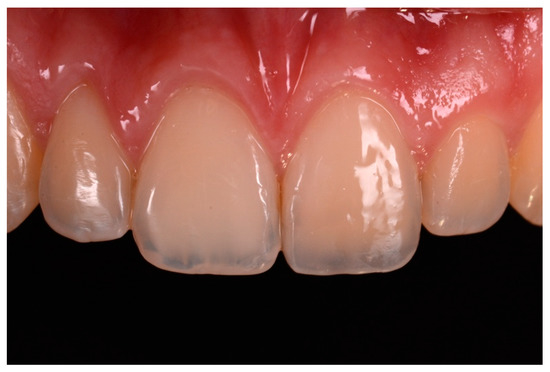

Figure 15.

Three months post-operative. Reprinted from Restauri diretti nei settori anteriori, G. Paolone, S. Scolavino, © 2021, with permission from Quintessence Publishing Italy.

Figure 16.

One year post-operative. Reprinted from Restauri diretti nei settori anteriori, G. Paolone, S. Scolavino, © 2021, with permission from Quintessence Publishing Italy.

Finishing and polishing procedures were performed with a diamond bur (WL 268 014 Horico, Berlin, Germany), silicone points (Identoflex, Kerr, Bioggio, Switzerland) brushes (Jiffy Goat Air Brushes, Ultradent Products, South Jordan, UT, USA), and diamond pastes (Diamond Polish Mint, Ultradent Products, South Jordan, UT, USA) (Figure 13 and Figure 14). Satisfactory clinical and radiographic outcome was considered satisfactory at 3-months, 1-year, and 5-years post-operative (Figure 15, Figure 16, Figure 17, Figure 18 and Figure 19).